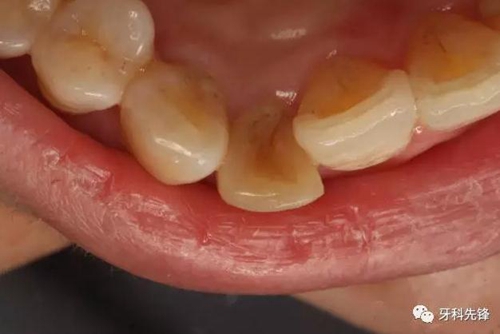

圖3。12的腭側(cè)未檢查有齲壞及畸形舌側(cè)窩,證明12牙根未發(fā)育完成是含牙囊腫影響所致。